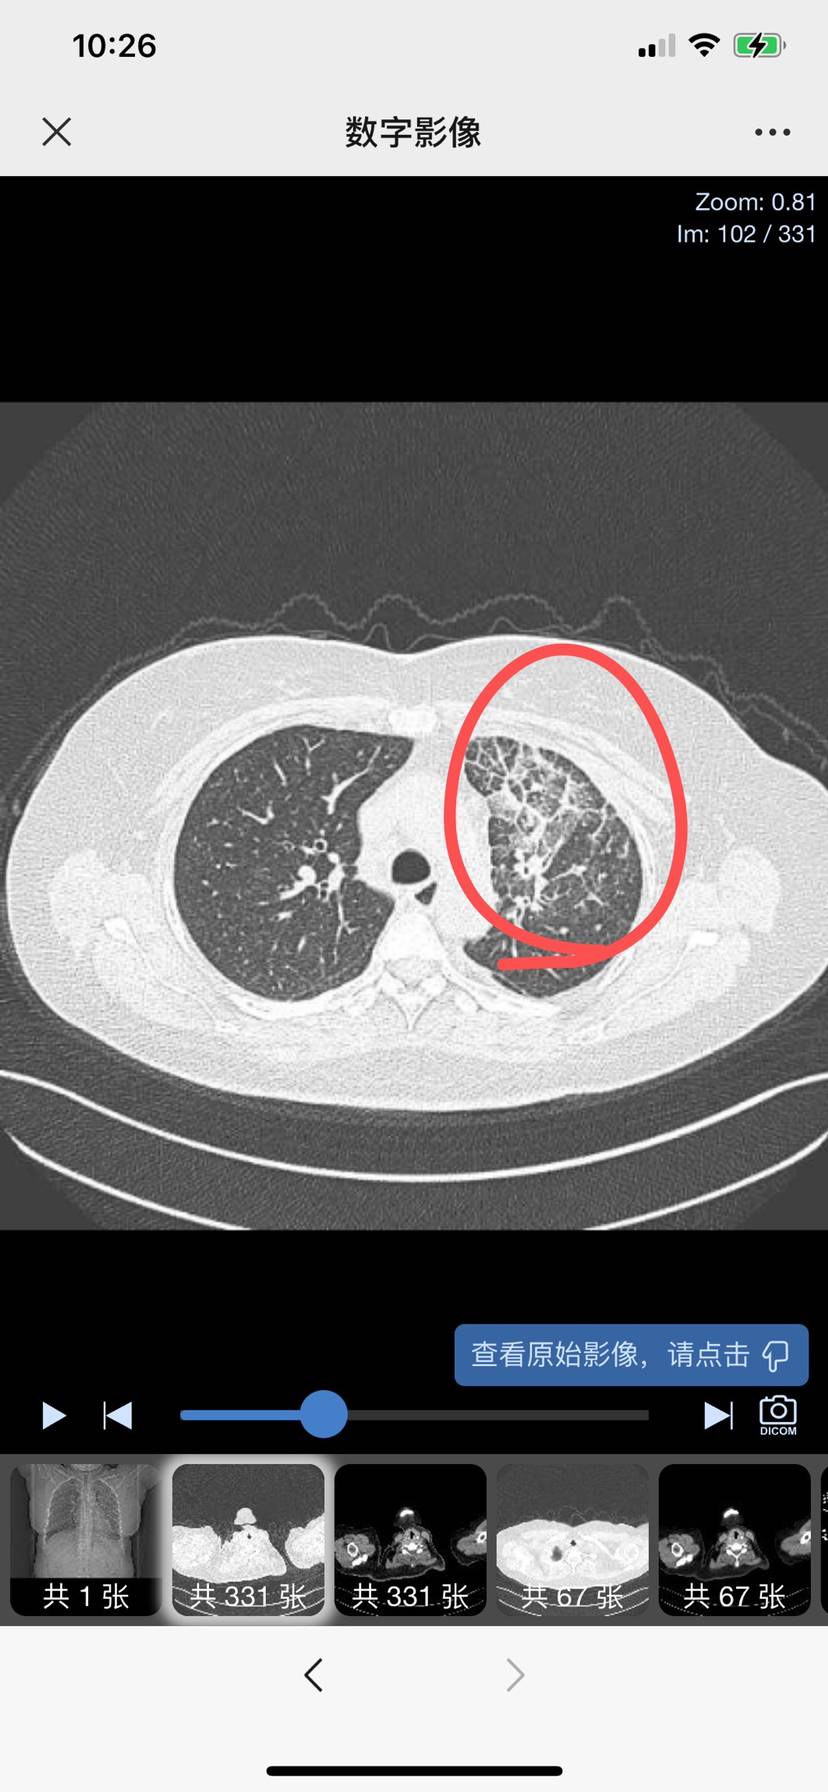

近期片子

(复查:2023年12.18 出现有部分小结节稍有增大 ,单癌性淋巴管较前好转,询问主任说暂时稳定暂不考虑换方案)

2024年1月20开始出现咳嗽流鼻涕、发烧,吃了退烧药当天退烧,检查c反应蛋白高,目前检测肺炎支原体感染,已在医院打消炎针10天,已经不发烧啦。但左上肺癌性淋巴管炎进展,医生建议稳定后再做穿刺。